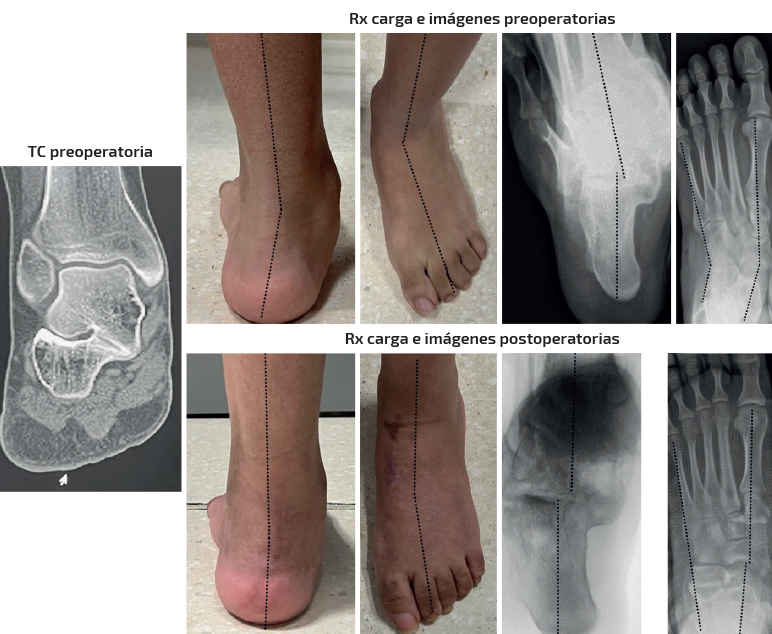

Caso 2 (Figura 5)

Se trata de un paciente varón de 26 años. Clínica de dolor medial y pinzamiento subfibular. Coalición talocalcánea ósea completa. Deformidad en plano, valgo y abducto. Tipo IIB de Myerson. Tratamiento: doble osteotomía del calcáneo (alargamiento de la columna externa + deslizamiento medial) + osteotomía de Cotton. Aloinjerto liofilizado de cresta. Seguimiento: 2,5 años. Mejoría en la alineación clínica y el dolor. Destaca la mejoría en los parámetros radiológicos del retropié tanto dosoplantares como sagitales a pesar de la coalición ósea. Nota: caso cedido por Dr. F. J. Carrillo Piñero).

Caso 3 (Figura 6)

Se trata de una paciente mujer de 15 años. Afecta de coalición talocalcánea fibrocartilaginosa con deformidad en plano, valgo y abducto con subtalar rígida. Dolor medial y en sinus tarsi. Tipo IB de Myerson. Tratamiento: doble osteotomía (alargamiento de la columna externa + deslizamiento medial) en el calcáneo y osteotomía pronadora según Cotton + alargamiento del tríceps sural de tipo Strayer. Aloinjerto liofilizado de cresta. Seguimiento: 1,5 años. Mejoría de la alineación clínica y del dolor preoperatorio. Obsérvese cómo en este caso el astrágalo mantiene su flexión plantar en la radiografía lateral pero se ha corregido el abducto y el valgo clínicamente y en la radiografía dorsoplantar. También ha mejorado la altura del arco clínica y en la radiografía anteroposterior (AP) de tobillo (aumento de la altura de la interlínea del tobillo comparativa entre ambos tobillos pre- y postoperatoriamente).